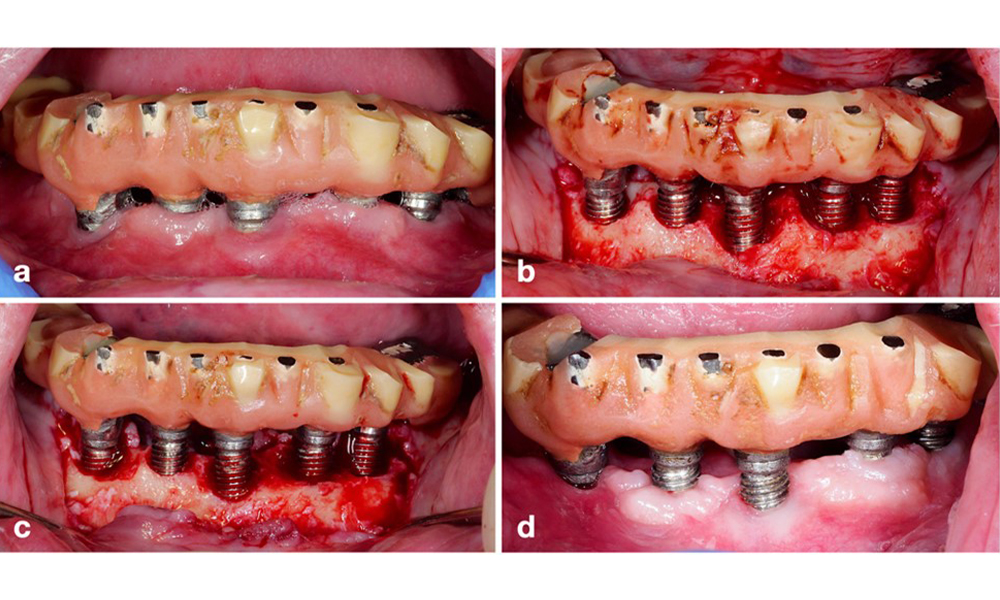

The World Workshop on the Classification of Periodontal and Peri‐Implant Diseases and Conditions from 2017 established diagnostic criteria for peri-implant mucositis and peri-implantitis (Renvert et al. 2018). Peri-implant mucositis is defined as (1) presence of inflammation around the implant (i.e., redness, swelling, line or drop of bleeding within 30 seconds of probing), combined with (2) no additional bone loss after initial healing (figure 1).

Implant in position 26 with peri-implant mucositis (a–c). The probing depth value of 5 mm (b) remains consistent with the measurement taken a few weeks after placing the prosthetic reconstruction. There is bleeding on probing (c) but the radiograph indicates no additional bone loss beyond what is expected for marginal bone remodelling (d).

Figure 1. Implant in position 26 with peri-implant mucositis (a–c). The probing depth value of 5 mm (b) remains consistent with the measurement taken a few weeks after placing the prosthetic reconstruction. There is bleeding on probing (c) but the radiograph indicates no additional bone loss beyond what is expected for marginal bone remodelling (d).

Peri-implantitis is identified by (1) signs of inflammation similar to mucositis, (2) radiographic evidence of bone loss after initial healing and (3) an increase in probing depth compared to measurements taken shortly after placing the prosthetic reconstruction (figure 2). In the absence of previous radiographs, radiographic bone level of ≥ 3 mm along with bleeding on probing and probing depths ≥ 6 mm, indicates peri‐implantitis.

Full-arch restoration with peri-implantitis of varying degrees at some implants. The implant in position 21 is severely affected with probing depths up to 9 mm (a), bleeding on probing, and suppuration from the peri-implant sulcus and a vestibular fistula (b–c); the radiograph shows approximately 50 % bone loss for the implant with peri-implantitis in position 21, while the implant in position 23 shows limited bone loss, corresponding approximately to what can be expected after initial healing for this type of implants (d).

Figure 2. Full-arch restoration with peri-implantitis of varying degrees at some implants. The implant in position 21 is severely affected with probing depths up to 9 mm (a), bleeding on probing, and suppuration from the peri-implant sulcus and a vestibular fistula (b–c); the radiograph shows approximately 50 % bone loss for the implant with peri-implantitis in position 21, while the implant in position 23 shows limited bone loss, corresponding approximately to what can be expected after initial healing for this type of implants (d).

The expected bone loss after initial healing attributed to marginal bone remodelling, varies based on factors such as the implant system or type. For instance, 1–2 mm bone loss is generally considered “normal” for bone level implants with an external connection (figure 2d, implant in position 23).